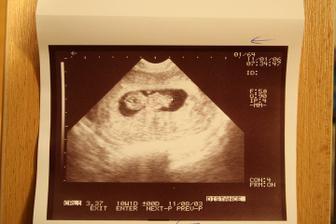

6.1.2011 třetí kontrola (11tt) - dostali jsme těhu průkajdu, byli jsme na odběru krve, vyšetření moči a dostali jsme tři ultrazvuky. Mimísek měří 33mm